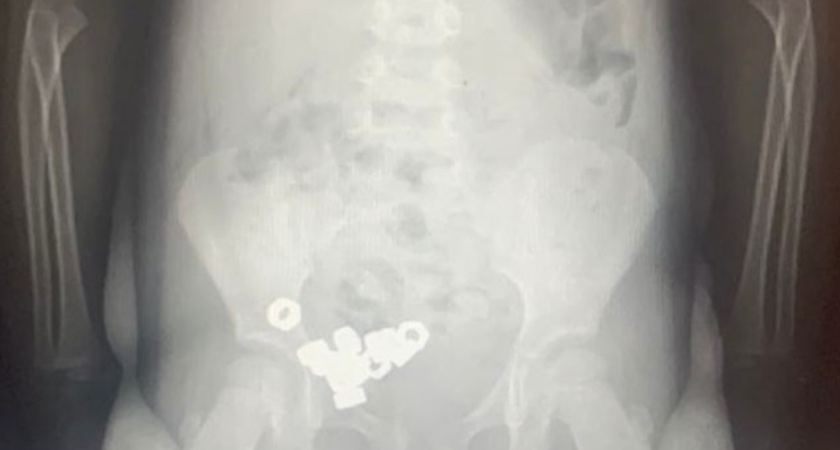

Врачи областной детской клинической больницы №2 помогли трёхлетнему мальчику, который проглотил шестнадцать маленьких гаек. Об этом сообщили в министерстве здравоохранения Воронежской области.

Родители привезли ребёнка в приёмное отделение, заподозрив, что он мог проглотить что-то постороннее. Симптомов не было, малыш чувствовал себя спокойно, но врачи сразу направили его на рентген. Снимок показал десятки чётких контуров металлических предметов – в желудке и кишечнике находилось 16 гаек.

Мальчика оставили в больнице под наблюдением. Опасность состояла в том, что инородные предметы могли вызвать травмы или закупорку. Врачи выбрали щадящий способ – без операций: назначили диету, отдых и постоянный контроль. Каждый день ребёнку делали рентген, чтобы убедиться, что гайки постепенно выходят естественным путём.